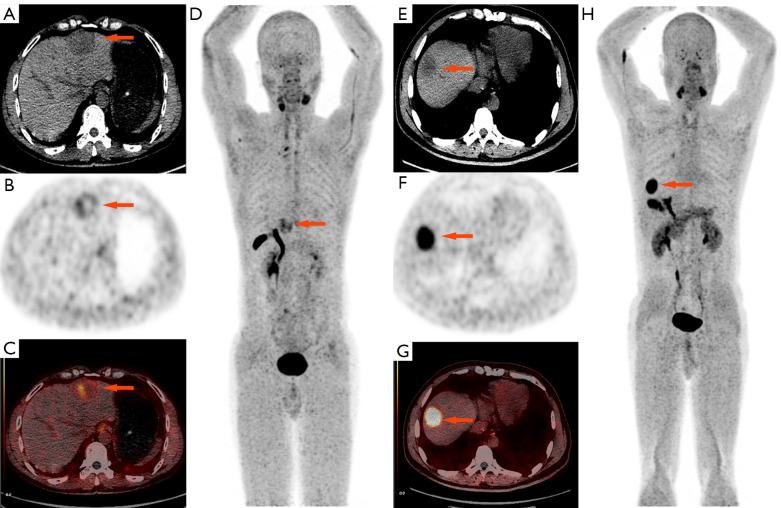

Accurately differentiating hepatocellular carcinoma (HCC) from intrahepatic cholangiocarcinoma (ICC) is essential for therapeutic decision-making. This study aimed to explore the value of Fluor 18 (F)-conjugated fibroblast-activation protein inhibitor (FAPI-42) positron emission tomography-computed tomography (PET/CT) in distinguishing HCC from ICC preoperatively.

A total of 48 patients (age 55.4±10.8 years; 35 males and 13 females), including 28 in the HCC and 20 in the ICC group, were included. Univariate analysis revealed significant differences in clinical indicators such as gender, platelet count, and hepatitis B surface antigen, carbohydrate antigen 19-9 (CA19-9), and alpha fetoprotein (AFP) levels between the groups (P<0.05). Metabolic parameters including the maximum standardized uptake value (SUVmax), the total lesion-FAPI (TL-FAPI), and the target-to-background ratio (TBR) were statistically different between groups (P<0.01), and patients with ICC had higher values than those with HCC, while the FAPI tumor volume (FAPI-TV) was not statistically different (P>0.05). Multivariate binary logistic regression analysis identified the SUVmax (P=0.003) as an independent predictor for ICC, and the AUC of the regression-based diagnostic model for predicting ICC was 0.914 at an optimal cutoff value of 12.13, with a sensitivity of 85.0% and a specificity of 89.3%.

SUVmax is an independent predictor for ICC. With the optimal cutoff value of 12.13, F-FAPI-42 PET/CT indicates good diagnostic efficacy in distinguishing between HCC and ICC.